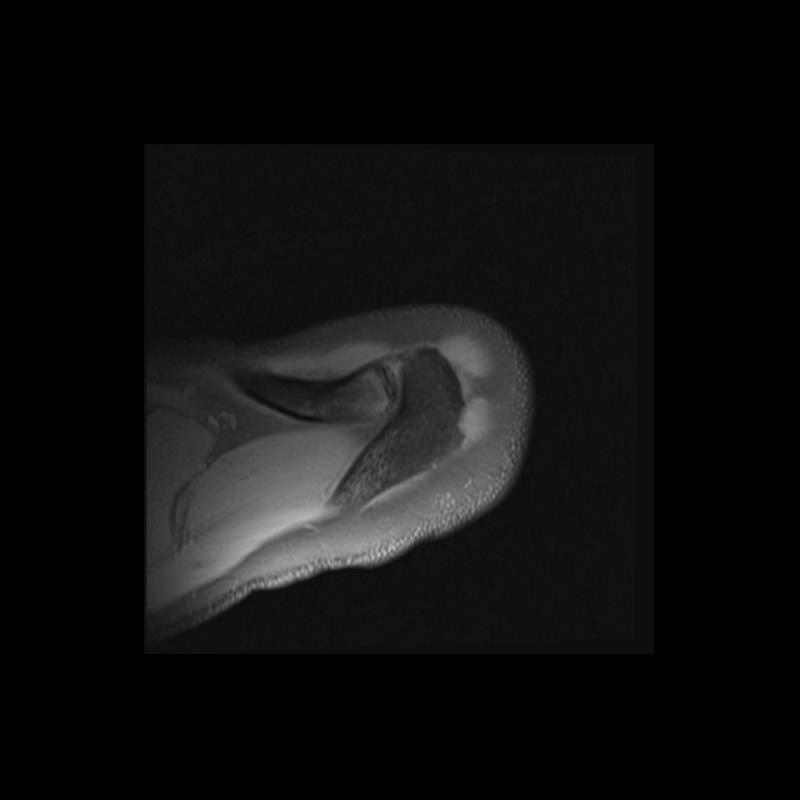

Shoulder MRI Anatomy